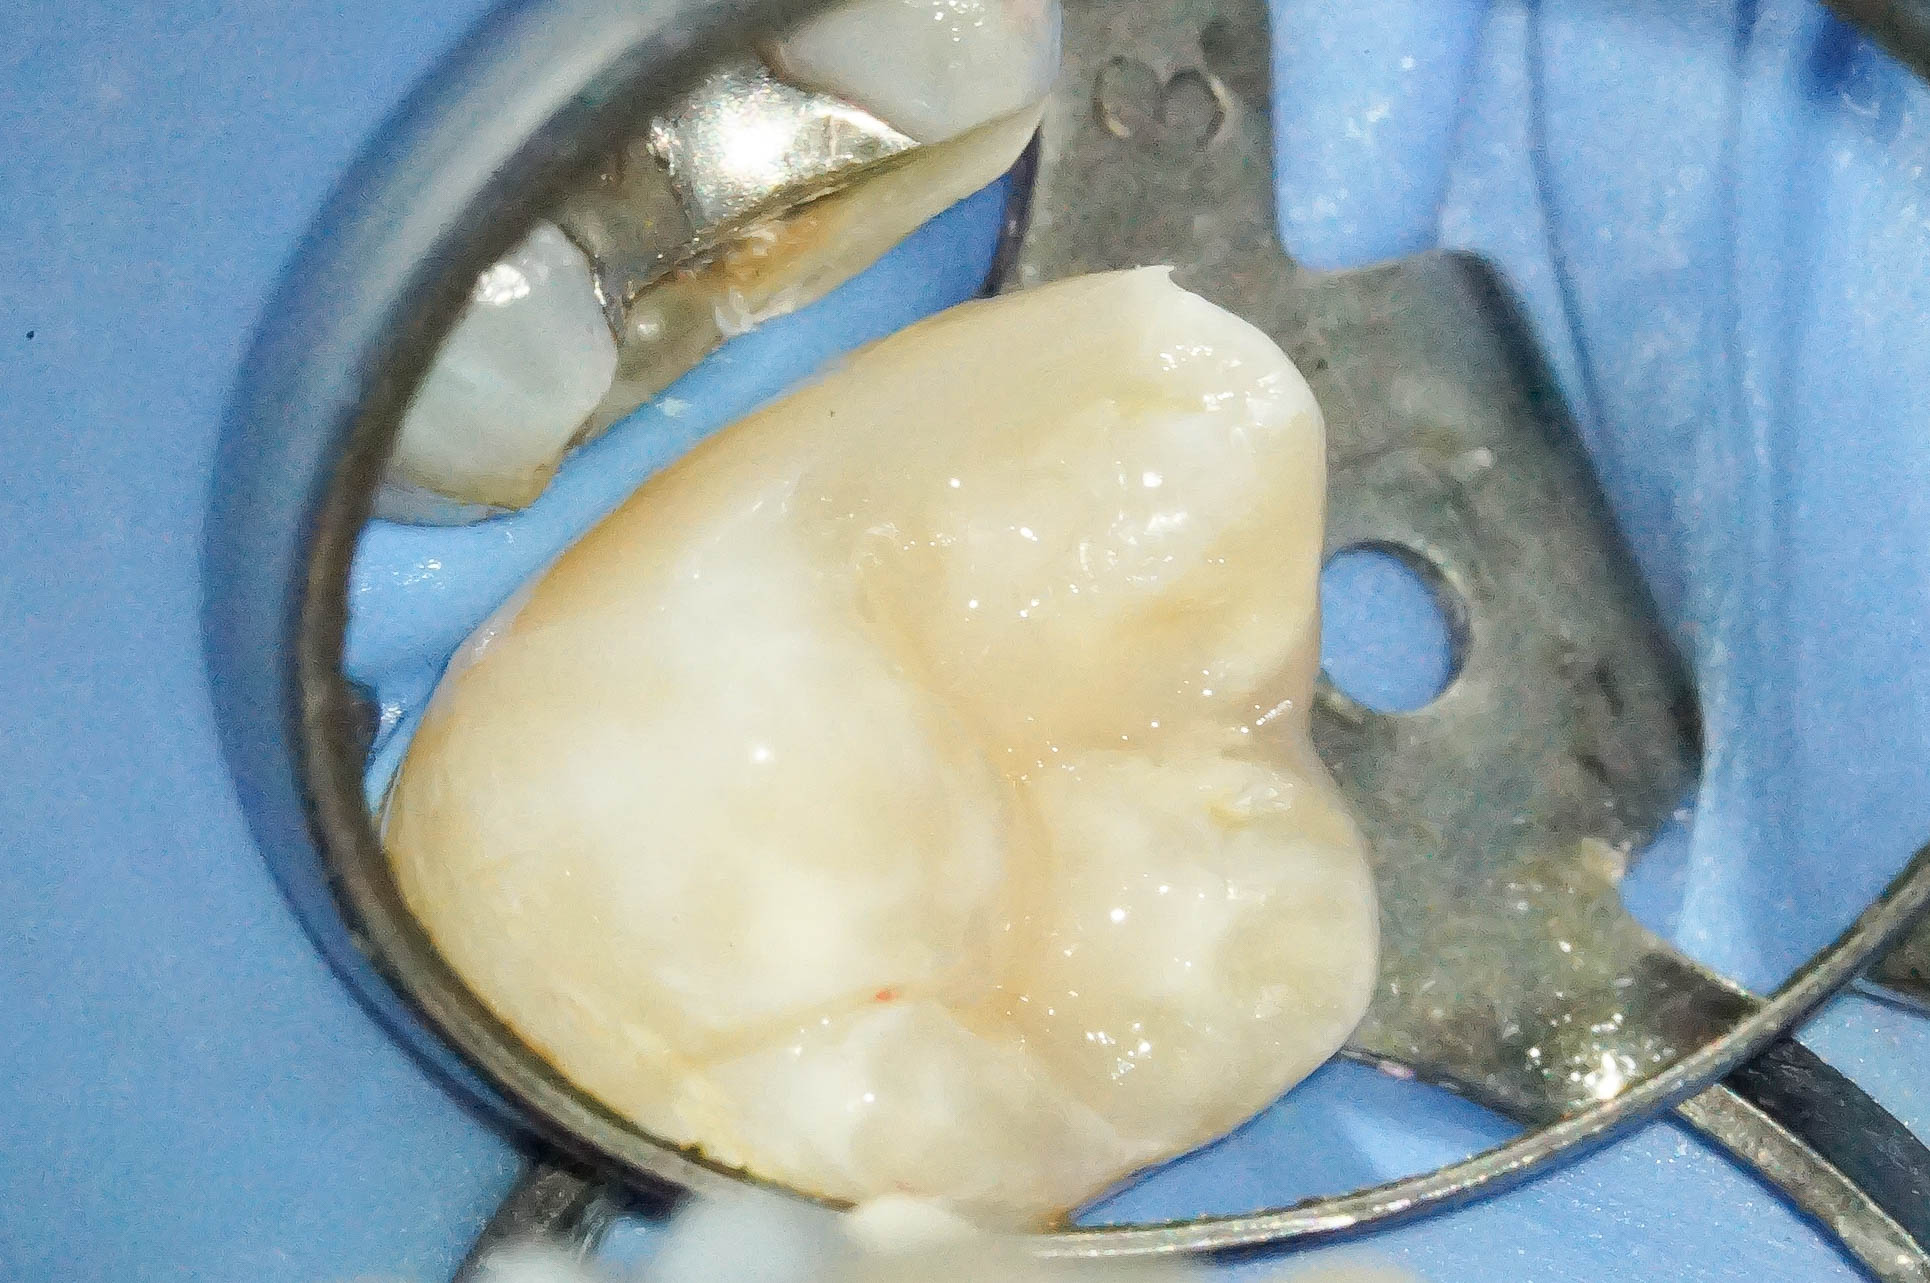

歯肉縁下ダイレクトボンディングを行った症例治療方法01

治療前の写真です。

他院でされたコンポジットレジンですが、フチの部分が黒くなっていたりと、

普段よく見かける一般的なコンポジットレジン修復の痕跡が見受けられます。